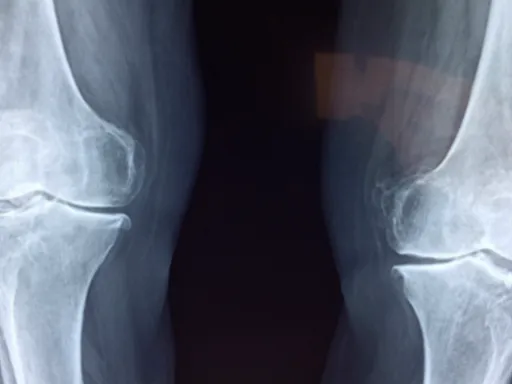

십자인대 파열 수술 후 회복은 단계별로 이루어지며, 각 단계에 따라 필요한 관리와 재활 방법이 다릅니다. 일반적으로 수술 직후부터 완전히 회복되기까지는 약 6개월에서 12개월이 걸리는데, 이는 개인의 상태에 따라 차이가 날 수 있습니다. 📅

십자인대 파열 수술 후 회복 과정에서 발생할 수 있는 합병증과 주의사항에 대해 알아보는 것은 매우 중요합니다. 수술 후에는 신체가 치유되는 과정에서 다양한 상황들이 발생할 수 있으며, 이를 잘 이해하고 대비한다면 회복 속도를 높일 수 있습니다. 예를 들어, 수술 후 약 5%의 환자에서 감염이 발생할 수 있습니다. 감염은 통증, 발열, 부기 등을 동반하며, 이러한 증상이 나타나면 즉시 전문의와 상담해야 합니다.